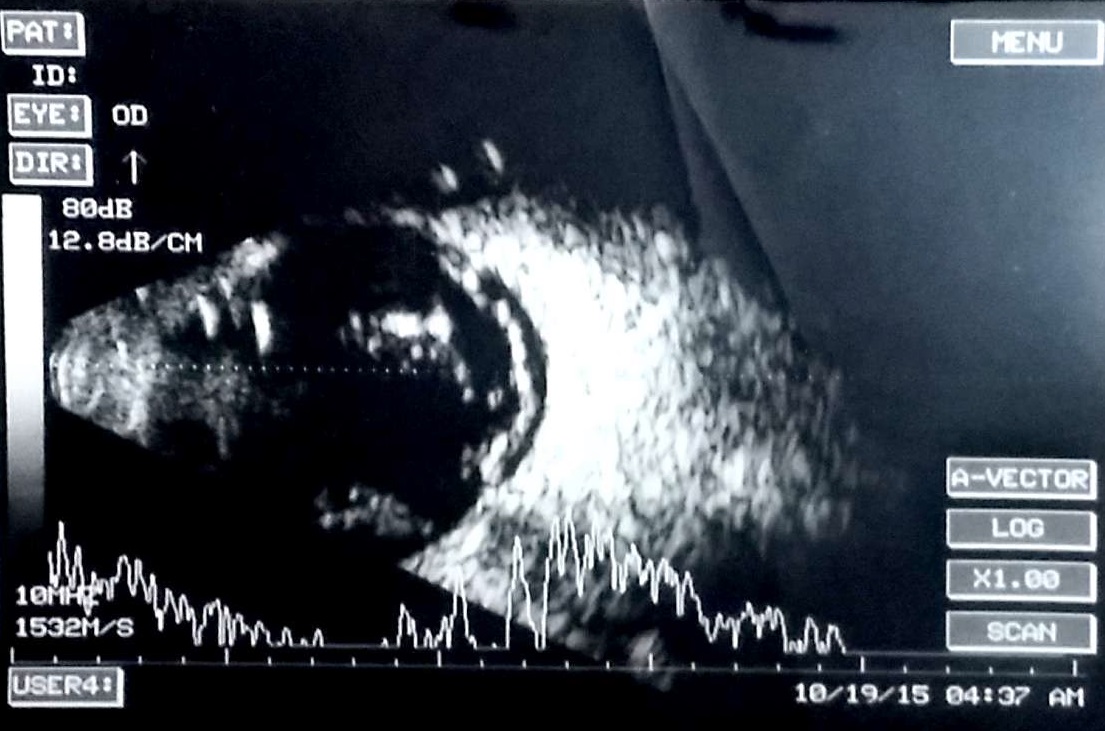

The retinal detachment is attached to the optic nerve head and has high amplitude and limited after movements